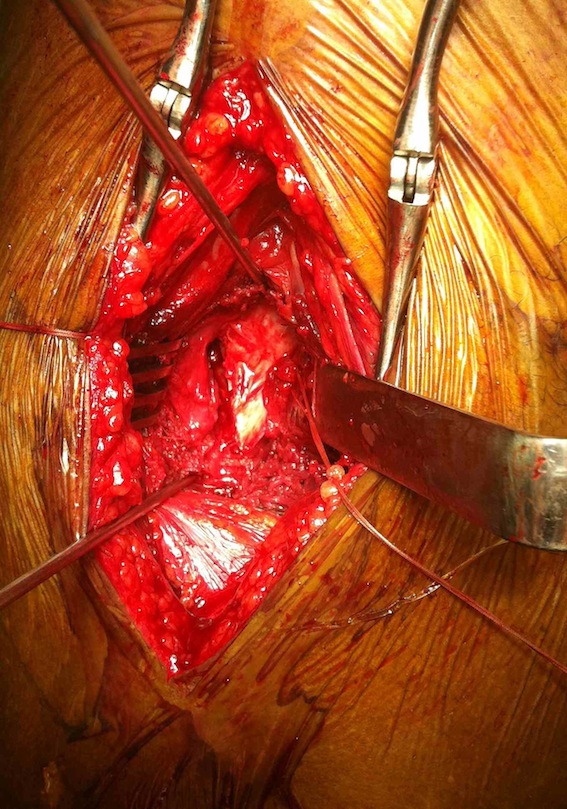

Technique Smith Petersen Approach

Vumedi technique Smith Petersen

Radiolucent table + floppy lateral with sandbag under affected hip

Vertical incision below ASIS

Superficial dissection

- between TFL (lateral) and sartorius (medial)

- interval more clear distally

- divide fasica over TFL with LFCN medial

- reflect muscle of TFL laterally

Deep dissection

- between G medius laterally and direct head rectus femoris medially

- +/- tenotomy of direct head rectus femoris

Smith Petersen anterior approach, with capsulotomy and reduction with pins

Capsulotomy

- transverse limb at head neck junction to preserve blood supply

- vertical down centre of femoral head

- avoid dissecting superior aspect of femoral neck where major artery of MCFA runs

- tag and reflect capsule

- place retractors inside the capsulotomy to expose the femoral neck

- can place superior retractor on ilium